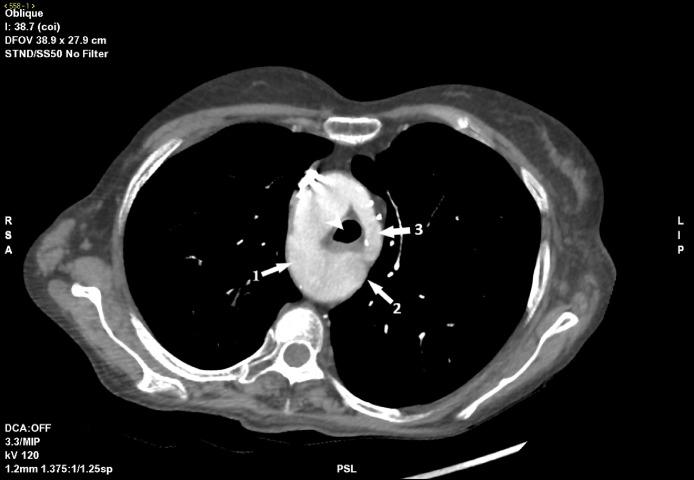

In this paper, we describe a rare case of double aortic arch with dominant right arch with focal narrowing of the distal left arch and descendent aorta's dilatation, associated with pulmonary embolism and left subclavian steal syndrome, found in a 59-year-old woman with a history of dysphagia, chest discomfort, and left arm claudication. Diagnosis of this condition was made with a sub-optimal pulmonary CT-angiography with a combination of characteristic features of double aortic arch and vascular rings. Being aware of these conditions is crucial to avoid misclassification and surgical and endovascular complications.

在本文中,我们描述了一例罕见的双主动脉弓病例,其右弓为主,左弓远端局灶性狭窄,降主动脉扩张,伴有肺栓塞和左锁骨下动脉盗血综合征,该病例见于一名有吞咽困难、胸部不适和左臂间歇性跛行病史的59岁女性。通过结合双主动脉弓和血管环的特征性表现的次优肺部CT血管造影对该疾病进行了诊断。认识到这些情况对于避免误诊以及手术和血管内并发症至关重要。